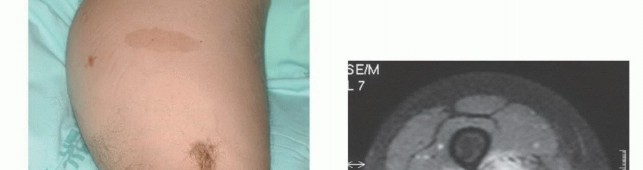

- كتلة أو تورم غير مؤلم: هذا هو العرض الأكثر شيوعًا. قد تلاحظ كتلة تحت الجلد في الجزء الخلفي من الفخذ. قد تكون هذه الكتلة ناعمة أو صلبة، وقد تنمو ببطء أو بسرعة. في البداية، قد لا تكون مؤلمة، مما يجعلها تُهمل أحيانًا.

تشخيص ساركوما الفخذ الخلفي

يتطلب تشخيص ساركوما الفخذ الخلفي تقييمًا دقيقًا وشاملًا لتحديد طبيعة الورم وحجمه ومداه، بالإضافة إلى أي امتداد محتمل للهياكل المحيطة. يعتمد الأستاذ الدكتور محمد هطيف على مجموعة من الفحوصات التصويرية والخزعات لضمان تشخيص دقيق يوجه خطة العلاج.

- التصوير بالرنين المغناطيسي (MRI): يُعد التصوير بالرنين المغناطيسي الأداة الأكثر فائدة في تقييم ساركوما الفخذ الخلفي. يوفر صورًا مفصلة للأنسجة الرخوة ويساعد في تحديد حجم الورم، وموقعه الدقيق، وعلاقته بالعضلات المحيطة، والعصب الوركي، والأوعية الدموية. كما يساعد في التمييز بين الأورام الحميدة والخبيثة.